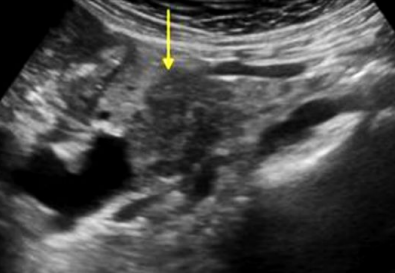

Describe this image

Diagnosis?

Transverse view of the pancreas

Pancreas appears to be swollen/enlarged with increased echogenicity and has peripancreatic fluid

Dx: acute pancreatitis